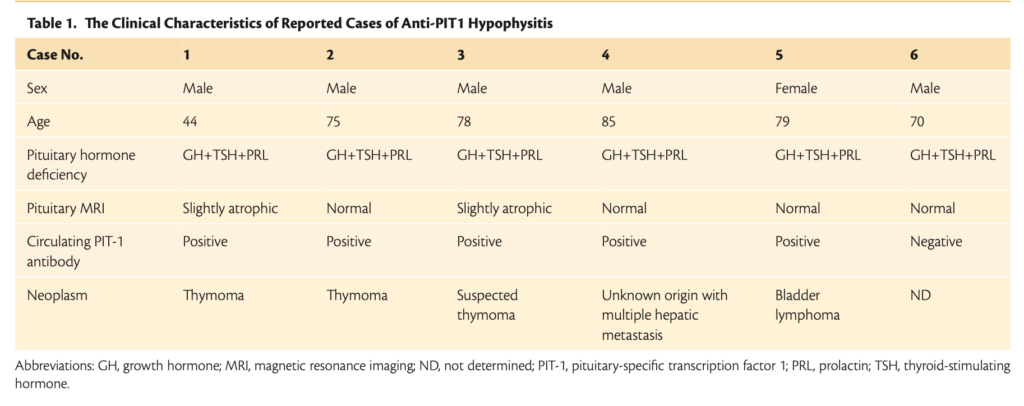

抗PIT-1下垂体炎は胸腺腫、悪性リンパ腫などに合併する傍腫瘍症候群。

胸腺腫によって引き起こされる新たな自己免疫疾患として神戸大学のグループが2017年に報告した。

胸腺腫瘍細胞において本来存在していないPIT-1(GH,TSH,PRLの産生に必要な転写因子)が異所性に発現することで免疫寛容破綻が生じ、PIT-1を特異的に攻撃する細胞障害性T細胞が産生され、下垂体GH,TSH,PRL産生細胞を特異的に障害すると考えられている。PIT-1に対する自己抗体が認められる。

その後悪性リンパ腫、原発不明の肝転移症例においても抗PIT-1下垂体炎の症例の報告が同グループからあり、胸腺腫に特異的な疾患ではない下垂体自己免疫疾患・傍腫瘍症候群と考えられている。

臨床的特徴

追加検査を行うとPRL・GHが検出下限値を示す。ACTHやLH・FSHは正常。

下垂体MRIでは前葉が軽度萎縮もしくは正常。

下垂体MRIでは明らかな異常が認められないため、原因不明の中枢性甲状腺機能低下症と診断されることが多い。しかし、造影MRIを行うと一部の患者では不均一な増強を伴うわずかに萎縮した下垂体前葉が認められる。

橋本病や1型糖尿病などの自己免疫疾患を合併する例もある。

②抗PIT-1抗体やPIT-1反応性T細胞の存在

③胸腺腫や悪性腫瘍の合併

ほとんどの患者は、胸腺腫や悪性腫瘍を合併している。

一般に、内分泌学的異常が悪性腫瘍の診断に先行する。